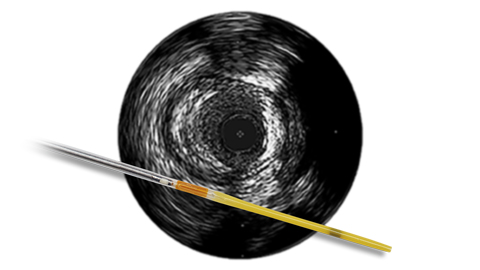

Angiography provides information on luminal characteristics of vessels, but does not provide a clear picture of the vessel and disease.

However, with IVUS guidance you can see more clearly and improve patient outcomes with informed pre-stent planning and post-stent optimization.1